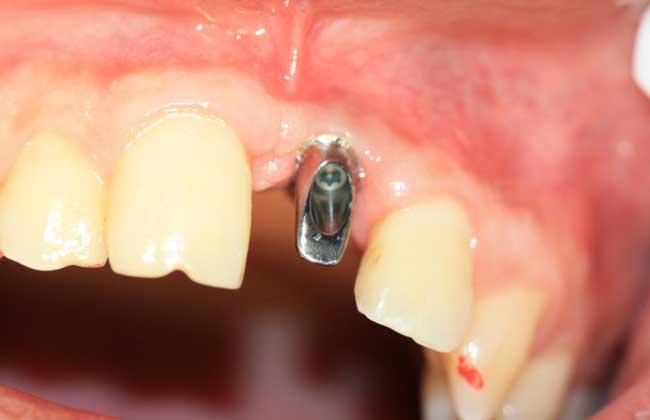

二期手术:基台植入

3-6个月后再次到院,拍片检查种植体和牙槽骨的结合情况,结合良好的话,就会进行二期的基台植入工作(部分人如果一期手术选择的是连同基台一同植入的话,就可以省略这步);然后等待1-2周后拆线;拆线完后等2周左右,牙龈愈合差不多了就可以进行牙冠取模。